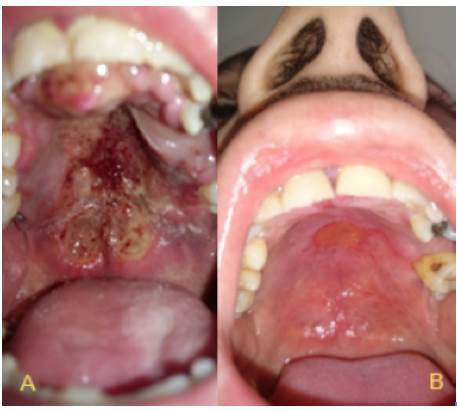

The final staging was T4, N1, M0, ECOG 1, IPI of low/intermediate-risk in a patient with poor health condition. The patient underwent chemotherapy with SMILE protocol (Table 1). Only 2 courses of SMILE were administered with adequate tolerance and some side effects, which were easily managed, such as queasiness, vomiting, weight loss and alopecia. Figure 4 shows the improvement of the lesion seven months after initiation of treatment; finally, after ten months of clinical and radiological surveillance, there was a complete remission of the lesions in oral and nasal cavity. In addition, the patient reported improvement of nasal obstruction and pain in the palate by 90%, but left amaurosis was persistent.